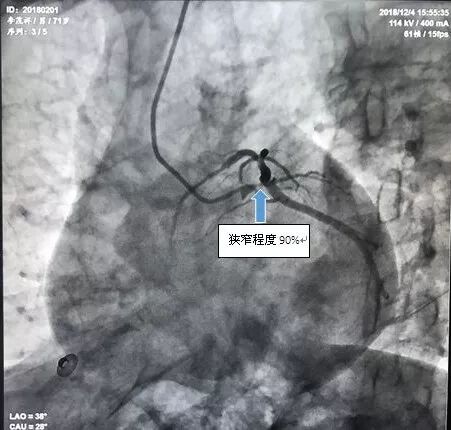

下午4点手术开始,造影显示李爹爹左主干严重狭窄 90%以上,命悬一线。在向病人家属交代病情后,王祥教授带领黄仲略主任和苏华俊主任迅速为患者植入支架,打通血管。血管打通仅花了20分钟。